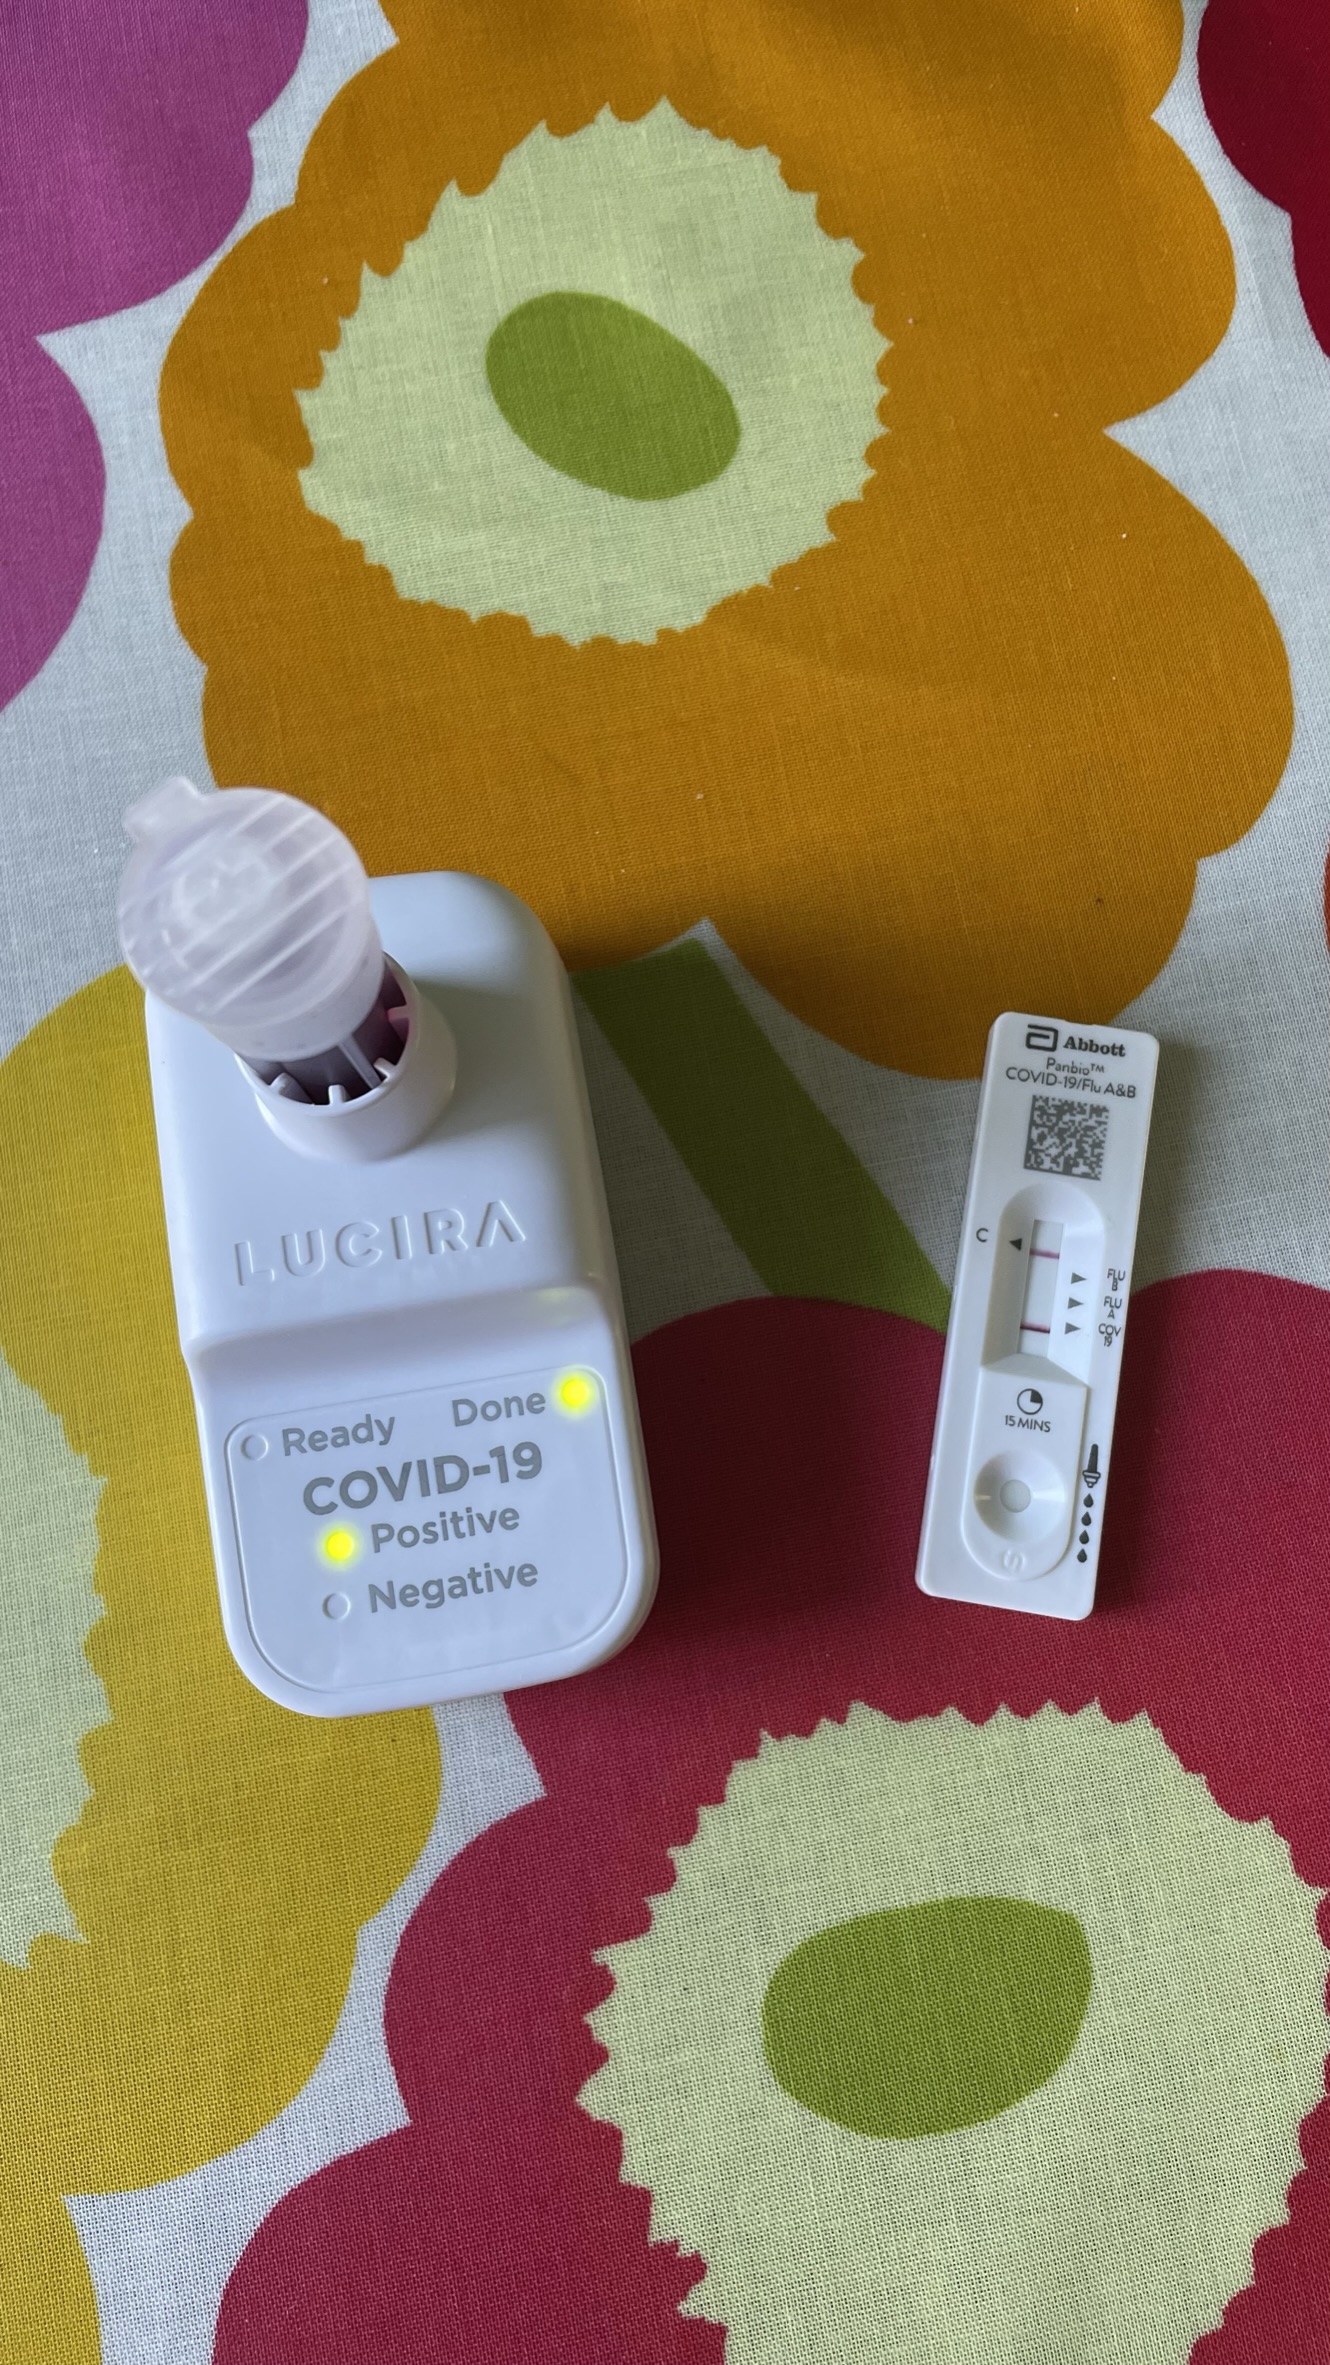

Darauf hätte ich gerne verzichtet

Meine Frau und ich hatten uns, gefühlt aus dem Nichts, mitten im Sommer mit COVID-19 infiziert. Alles daran war atypisch, die Zeit, die Symptome oder auch überhaupt die Infektionsquelle. Ändert aber nichts, die Antigen-Test und auch der bessere molekulare Test waren eindeutig. Die Erkrankung selbst war für uns beide an sich nicht so schwer, aber mitten im Sommer in einer täglich heißer werdenden Wohnung krank zusammen zu siechen, war trotzdem blöd. Ich selbst hatte an 12 Tagen durchgängig positive COVID-19-Tests, weit mehr als die typische knappe Woche. Obwohl ich gefühlt nicht stark erkrankt war, hatte COVID-19 doch starke Auswirkung auf meine Fitness und irgendwie habe ich seitdem leichte (eingebildete?) Atemprobleme, denn in Stresssituationen muss ich auch heute noch manchmal nach Luft schnappen. Vielleicht ist das aber auch nur mein Unterbewusstsein, dass neue Gadgets kaufen will, wie das Minidoc oder Sportgadgets für eine Atemkaliometrie.